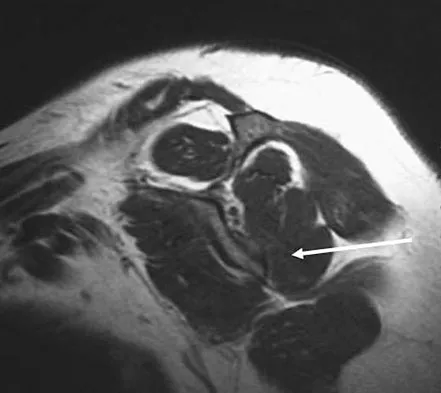

A 28-year-old man reports knee stiffness, swelling, and a constant ache that is worse with activity. Examination reveals an effusion, global tenderness, and warmth to the touch. Flexion is limited to 110 degrees. Figures 48a through 48d show sagittal T1-weighted, sagittal T2-weighted, axial T1-weighted fat-saturated gadolinium, and axial gradient echo MRI scans. Based on these findings, what is the most likely diagnosis?

Explanation